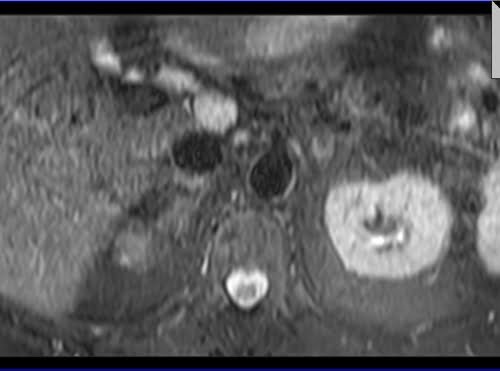

Adrenal MRI T2 TSE fat sat axial images